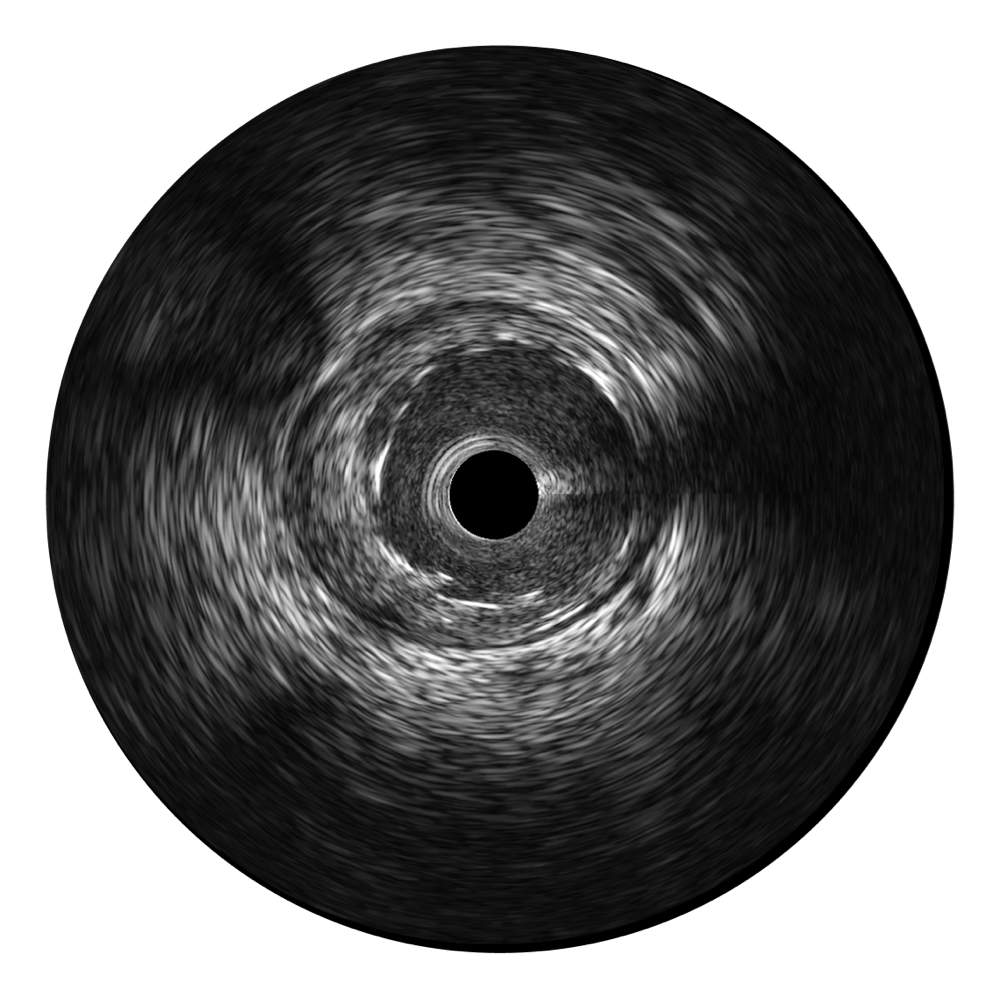

開立寬頻IVUS圖像

傳統(tǒng)IVUS圖像

對(duì)比傳統(tǒng)IVUS導(dǎo)管成像,開立寬頻IVUS圖像的近場(chǎng)支架梁顯影更細(xì)膩,遠(yuǎn)場(chǎng)中膜外血管仍清晰可辨,兼顧遠(yuǎn)中近,兼顧分辨力與穿透深度